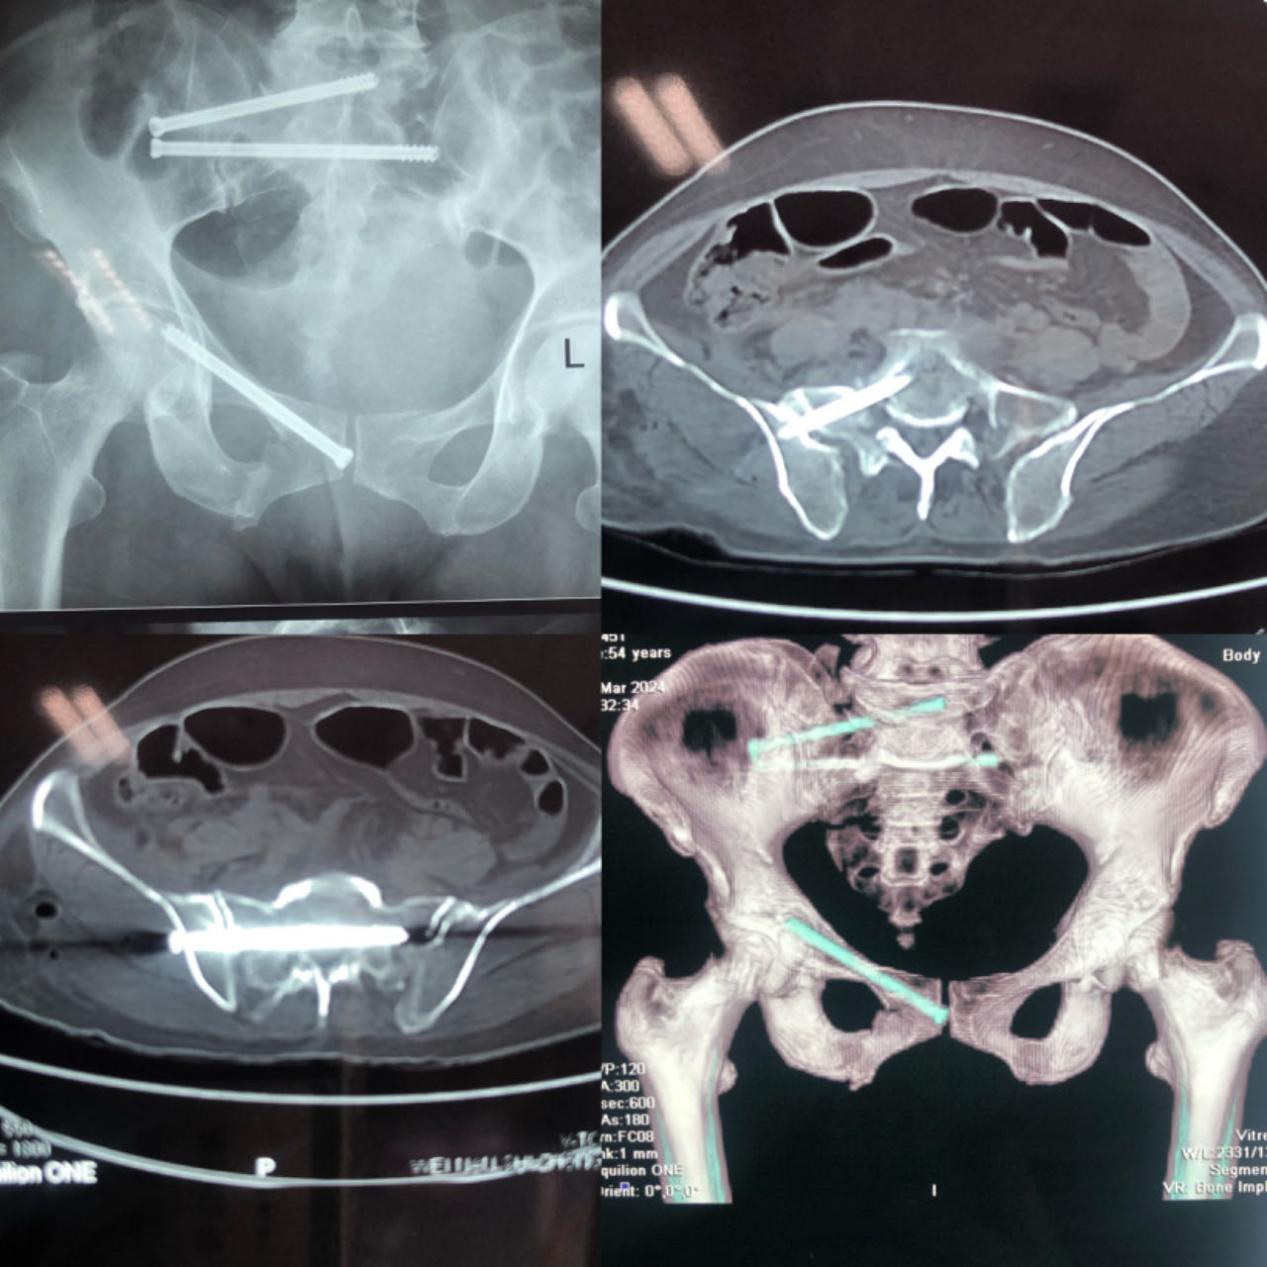

患者为一位54岁的女性,被重物砸伤2小时后来院诊治,经检查发现患者骨盆骨折(Ti1eB3型)、右侧骶骨骨折(denis2区)、双侧耻骨上下支骨折等。

考虑到患者伤情严重,同时伴有失血性贫血与低钾血症,影像学显示其骨盆双侧髂骨陡峭,骶骨纵行劈裂,且为变异性骶骨,经皮骶髂螺钉固定安全通道较难建立,长时间的闭合复位固定术中X线暴露也会给患者带来不小的损伤,传统的开放性手术会加剧失血程度,增加安全隐患。经科主任程福宏和主任医师郭宏军团队反复研讨后,决定在HoloSight机器人辅助下为患者进行微创手术。

术前,郭宏军医疗组进行充分准备,在患者右髂前上棘置入跟踪器,借助骨盆出口位及入口位的X光片,利用HoloSight智能规划出S1、S2置钉安全通道,并利用实时导引功能,成功将两枚空心螺钉植入理想位置。同样的方法,借助骨盆入口位及闭孔出口位的X光片,成功规划出逆行耻骨支螺钉通道,借助光学导引,成功拧入逆行耻骨支螺钉。术中,通过耻骨入口位于闭孔出口位验证,螺钉位于安全通道其深度均达到预期。

手术十分顺利,仅用时3小时,术后患者仅留下几个1cm左右的切口,大大减少了手术创伤及出血量。